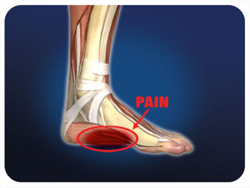

Ο πόνος στο πέλμα δεν είναι συχνά το αποτέλεσμα ενός τραυματισμού (π.χ. πτώση, στραμπούληγμα), αλλά τις περισσότερες φορές το αποτέλεσμα επαναλαμβανόμενης ή υπερβολικής καταπόνησης του πέλματος. Μπορεί να προέρχεται από φλεγμονή του πυκνού συνδετικού ιστού στο πέλμα του ποδιού (ο οποίος καταλήγει στην πτέρνα), γίνεται αισθητός στο κάτω μέρος της πτέρνας και καλείται πελματιαία απονευρωσίτιδα. Τον κίνδυνο εμφάνισης αυτού του προβλήματος επιτείνουν τα παπούτσια με κακή υποστήριξη της καμάρας ή μαλακές σόλες, καθώς και η αυξημένη πίεση στο πόδι.

Επιπλέον πιθανές αιτίες είναι οι σφιγμένοι γαστροκνήμιοι μύες, η καταπόνηση των ποδιών κατά το τρέξιμο μεγάλων αποστάσεων, το τρέξιμο σε κατηφόρα ή ανώμαλες επιφάνειες κ.λπ.. Τα οστεόφυτα στην πτέρνα συχνά συνοδεύουν την πελματιαία απονευρωσίτιδα, αλλά γενικά δεν αποτελούν την πηγή του πόνου. Εάν αντιμετωπίσετε κατάλληλα την πελματιαία απονευρωσίτιδα, τα οστεόφυτα πιθανότητα δεν πρόκειται να σας ενοχλήσουν ξανά. Η θυλακίτιδα της πτέρνας (φλεγμονή στο πίσω μέρος της πτέρνας) μπορεί να προκληθεί από σκληρή ή αδέξια προσγείωση στην πτέρνα, ή εξαιτίας πίεσης από τα παπούτσια.

Επιπλέον πιθανές αιτίες είναι οι σφιγμένοι γαστροκνήμιοι μύες, η καταπόνηση των ποδιών κατά το τρέξιμο μεγάλων αποστάσεων, το τρέξιμο σε κατηφόρα ή ανώμαλες επιφάνειες κ.λπ.. Τα οστεόφυτα στην πτέρνα συχνά συνοδεύουν την πελματιαία απονευρωσίτιδα, αλλά γενικά δεν αποτελούν την πηγή του πόνου. Εάν αντιμετωπίσετε κατάλληλα την πελματιαία απονευρωσίτιδα, τα οστεόφυτα πιθανότητα δεν πρόκειται να σας ενοχλήσουν ξανά. Η θυλακίτιδα της πτέρνας (φλεγμονή στο πίσω μέρος της πτέρνας) μπορεί να προκληθεί από σκληρή ή αδέξια προσγείωση στην πτέρνα, ή εξαιτίας πίεσης από τα παπούτσια.